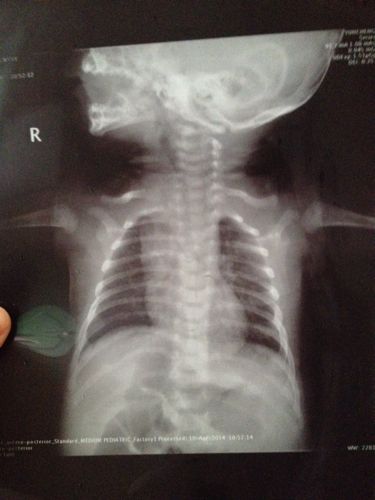

胸片是一种快速、无创、且信息量巨大的检查工具,对于新生儿,它通常是诊断以下疾病的首选或必要手段:

- 呼吸系统疾病: 如新生儿肺炎、肺透明膜病、湿肺等,可以观察肺部有无炎症、实变或积液。

- 先天性心脏病: 可以观察心脏大小、形态,评估肺部血流情况,为诊断提供重要线索。

- 胸腔畸形: 如先天性膈疝、胸廓畸形等。

- 气管插管位置确认: 对于需要呼吸机支持的新生儿,确认气管插管是否在正确位置至关重要。

- 评估病情和治疗效果: 在治疗过程中,可以通过胸片观察病情变化和治疗效果。